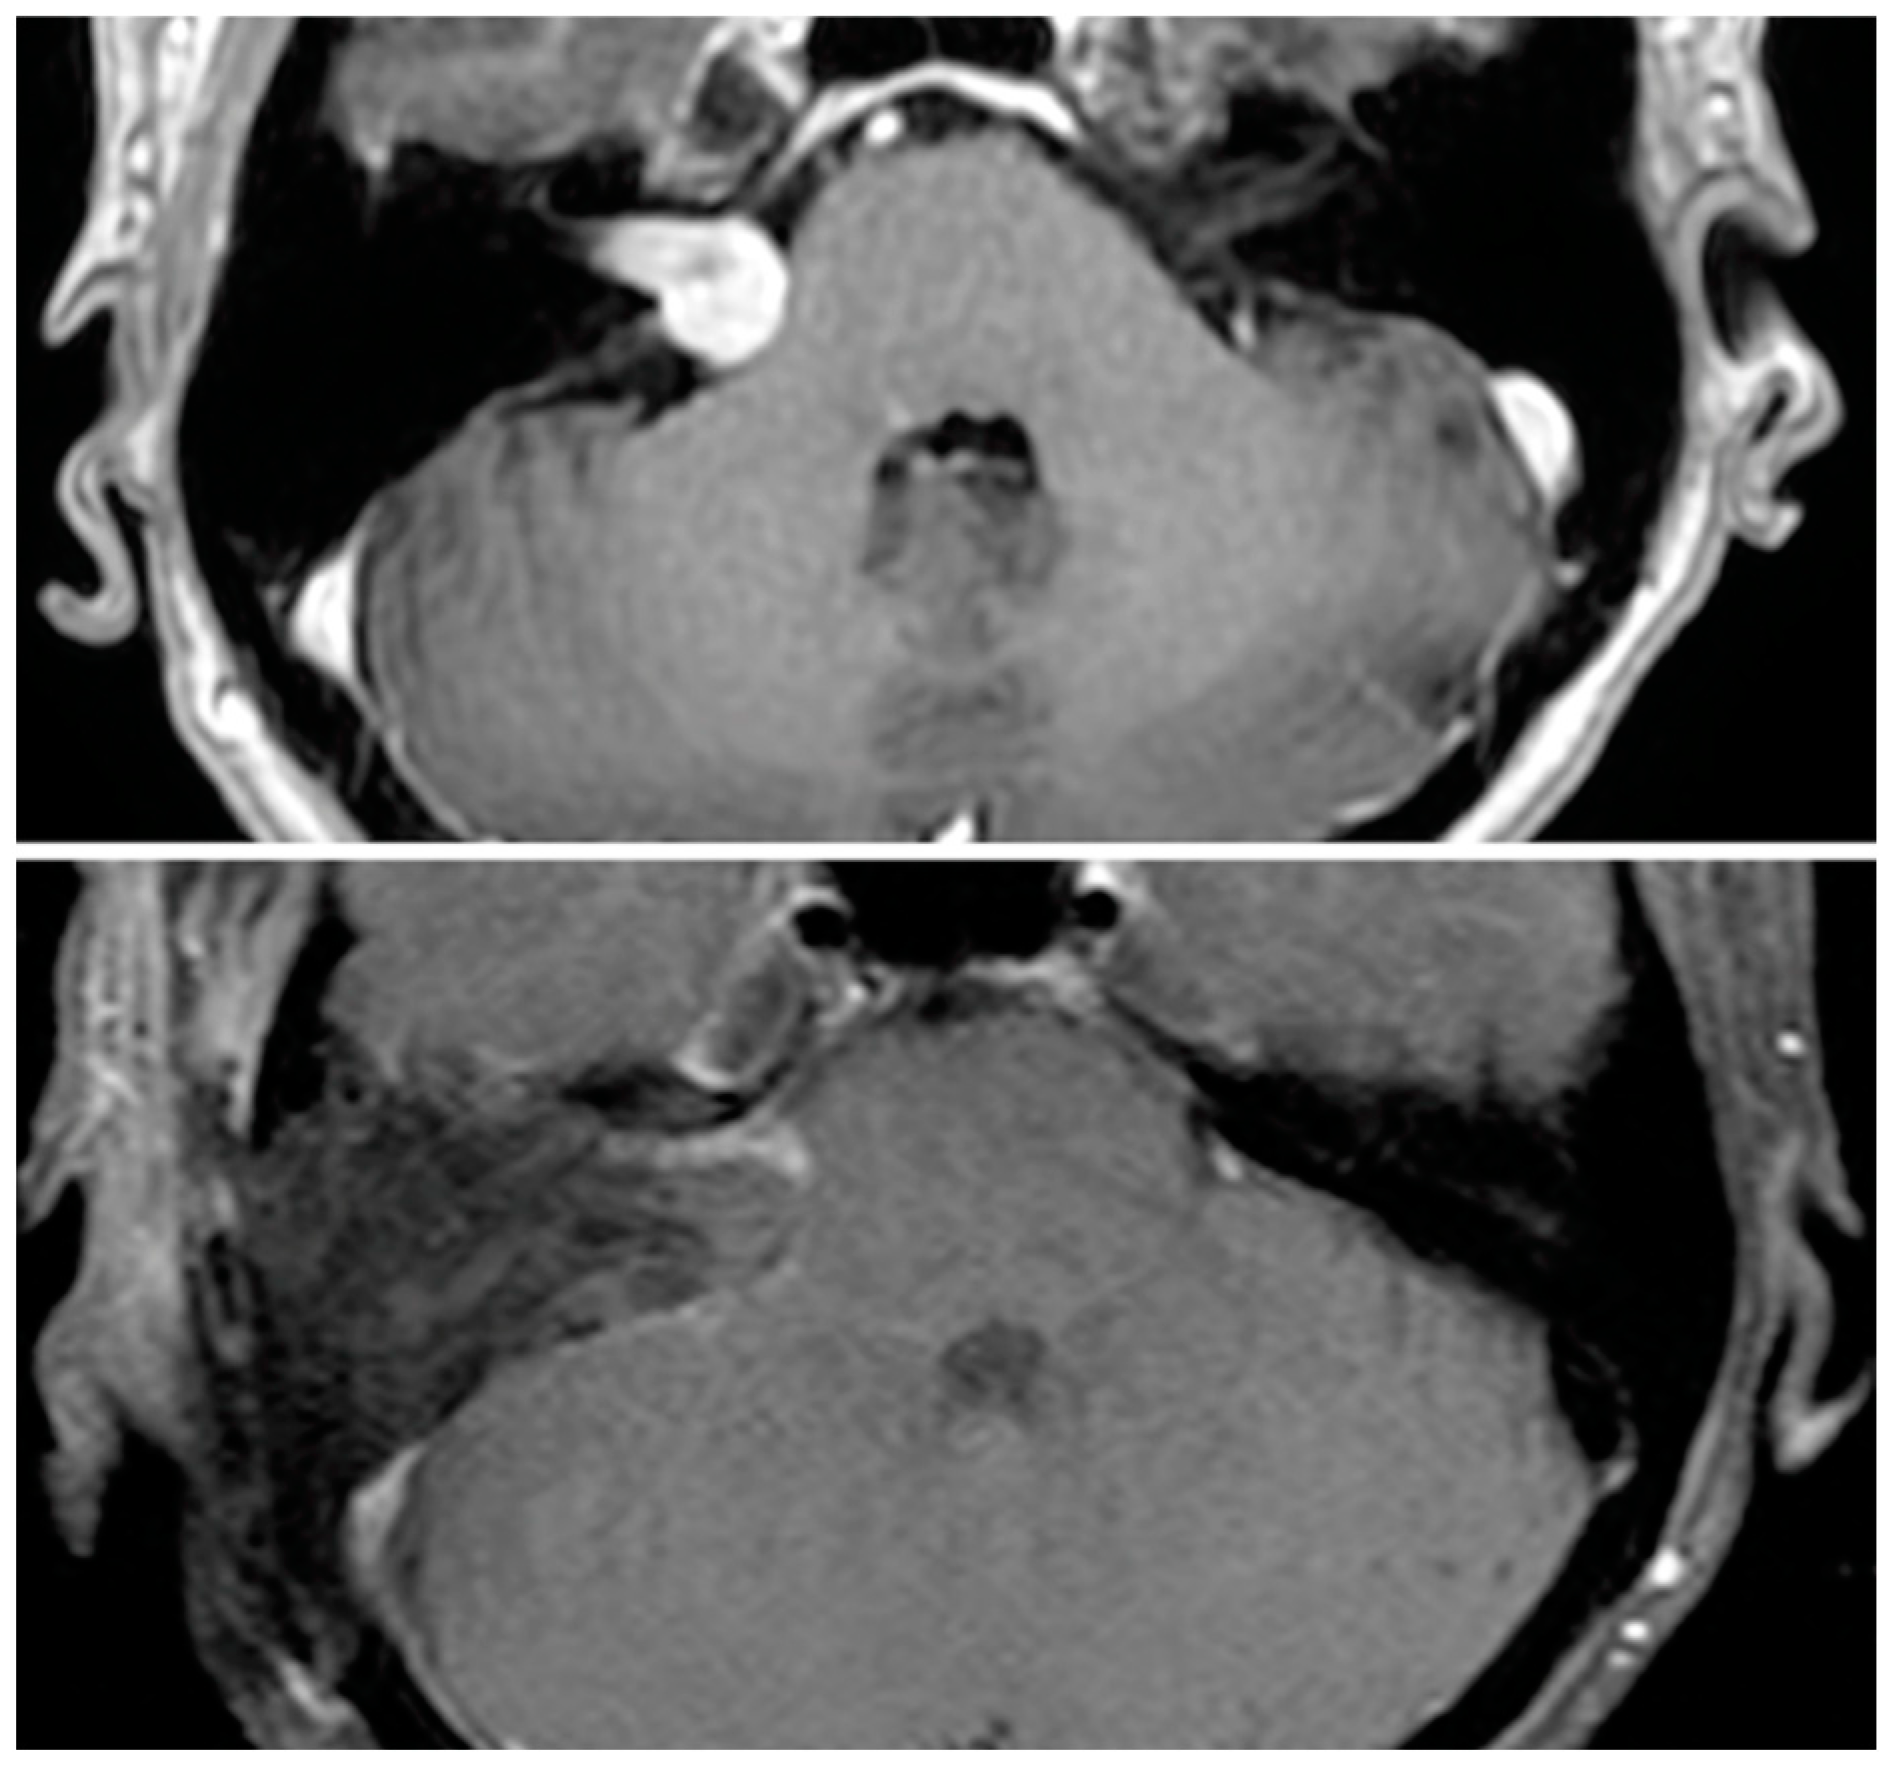

Volumetric analysis of residual tumors on the immediate post-operative MRI revealed that of twenty-two near-total cases, eight were radiographic GTR and nine were radiographic STR (mean volume ratio 11.9%), while five remained radiographic NTR (mean volume ratio 1.8%). Of the three sub-total cases, two were radiographic GTR while one remained radiographic STR. Of cases with a radiographic residual, seven had linear and eight had nodular residuals. Figure 1 demonstrate examples of these pre- and post-operative tumor images. Overall, radiographic assessment changed the degree of resection in nineteen cases (17.4% of all cases and 76% of cases with a residual).

Figure 1. Pre-operative MRI (top panel) shows right sided vestibular schwannoma that was resected (bottom panel) using a translabyrinthine approach. While this was assessed as a near-total resection, post-operative volumetric analysis classified the residual as subtotal resection (7.9% of original tumor volume).